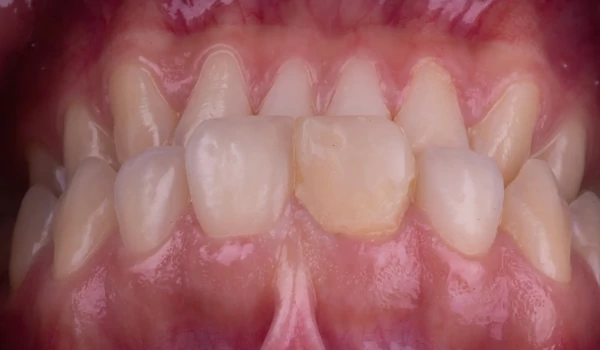

| A ragasztás maga a háromkomponensű PANAVIA™ V5 cementtel történt (23–28. ábra): Az előkészített fogstruktúrát és a felépítményt a PANAVIA™ V5 Tooth Primer-rel kezelték, a korona belső felszínét pedig a CLEARFIL™ CERAMIC PRIMER PLUS-szal. Végül a PANAVIA™ V5 Universal (fehér) cementet kinyomták a koronába, majd a koronát a helyére illesztették. A felesleges cementet a legjobb a gél fázisban eltávolítani – azaz a végső fényre keményítés előtt, 3-5 másodperces rövid polimerizáció után. Alternatív megoldásként közvetlenül a restauráció behelyezése után is eltávolítható ecsettel vagy hasonló eszközzel. Ebben az esetben az első lehetőséget választották. A kezelés eredményét a kofferdám eltávolítása, valamint a végső klinikai és esztétikai értékelés után a 29. ábra mutatja. |

29. ábra. A kezelés eredménye közvetlenül a kofferdám eltávolítása után. |

KonklúzióA beavatkozás célja egy traumásan sérült fog megőrzése volt – mind funkcióban, mind esztétikában. A sikerhez kulcsot jelentett a CLEARFIL MAJESTY™ ES-2 Premium erős, stabil alapja és a PANAVIA™ V5 egyik legmegbízhatóbb ragasztórendszere kuraraynoritake.eu. |